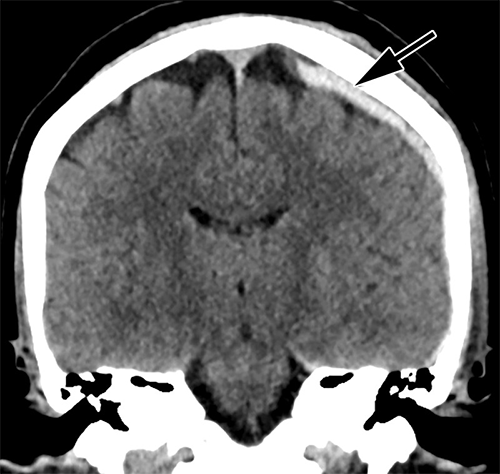

Review of reports by two experienced emergency radiologists revealed that both intimate partner violence and suicidal behavior played independent roles in doubling the overall injury rate compared to that of patients without a history of intimate partner violence or suicidal behavior. Patients with intimate partner violence often sustained head, face, neck and upper limb injuries—areas commonly hurt during assaults.

Intimate partner violence patients with suicidal behavior suffered over six times as many head/face/neck injuries, almost four times as many spinal fractures, three times as many deep injuries, and twice as many upper extremity injuries. These patients experienced almost twice as many severe injuries and three times as many mild injuries.

Figure 2. Head CT of intimate partner violence patient with left-sided parietal subdural hematoma (arrow).